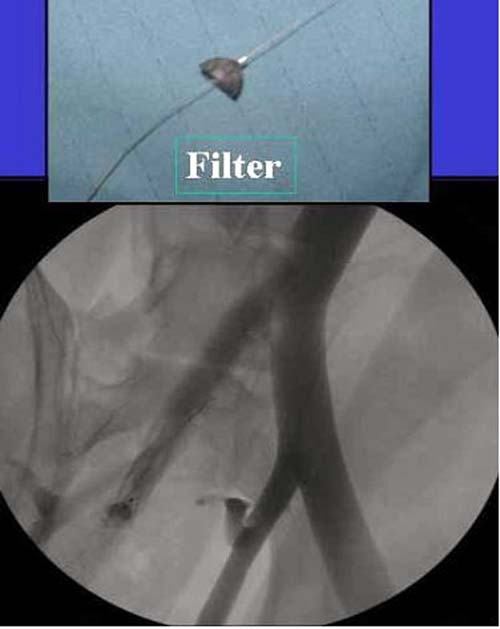

Работаем вместе с хирургами-травматологами (в штатах все травмированные больные поступают, как больные хирургической службы, ортопед выступает в качестве консультанта), т.е. мы даем рекомендации о проведении профилактики тромбоза, совместно решаем о проведении фильтра - вена кава фильтр (см. приложение).

Если вена кава фильтр, хирурги проводят эту процедуру, а медикаментозную профилактику назначаем сами.